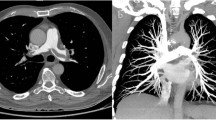

Objective image quality

Key findings for objective image quality are shown in Table 2, with corresponding p-values listed in Table 3. Enhancement in the pulmonary arterial tract and aortic tract was lowest in protocol D, where the least CM was administered, and highest in protocol A, where the most CM was injected. However, there were no significant differences in average pulmonary arterial attenuation between the two high-flow protocols (A and B with 5 ml/s), and between the two protocols with intermediate contrast volume (B and C with 50 ml). Protocol D showed significantly lower SNR and CNR-values in the pulmonary arterial tract compared to all other protocols, while no significant differences were observed between protocols A, B and C concerning pulmonary arterial SNR or CNR. For the aortic tract, there was no significant difference in attenuation and SNR between protocols A and B, while aortic enhancement and SNR decreased significantly with lower flow or lower CM volume in protocols C and D. Aortic tract CNR was significantly lower for protocol D compared to all other protocols, whereas protocols A, B and C showed no significant differences. Venous tract attenuation was highest for protocol D, and lowest for protocol B, with intermediate values in protocols A and C. Figure 2 demonstrates exemplary CTPA and iodine map images for each protocol.